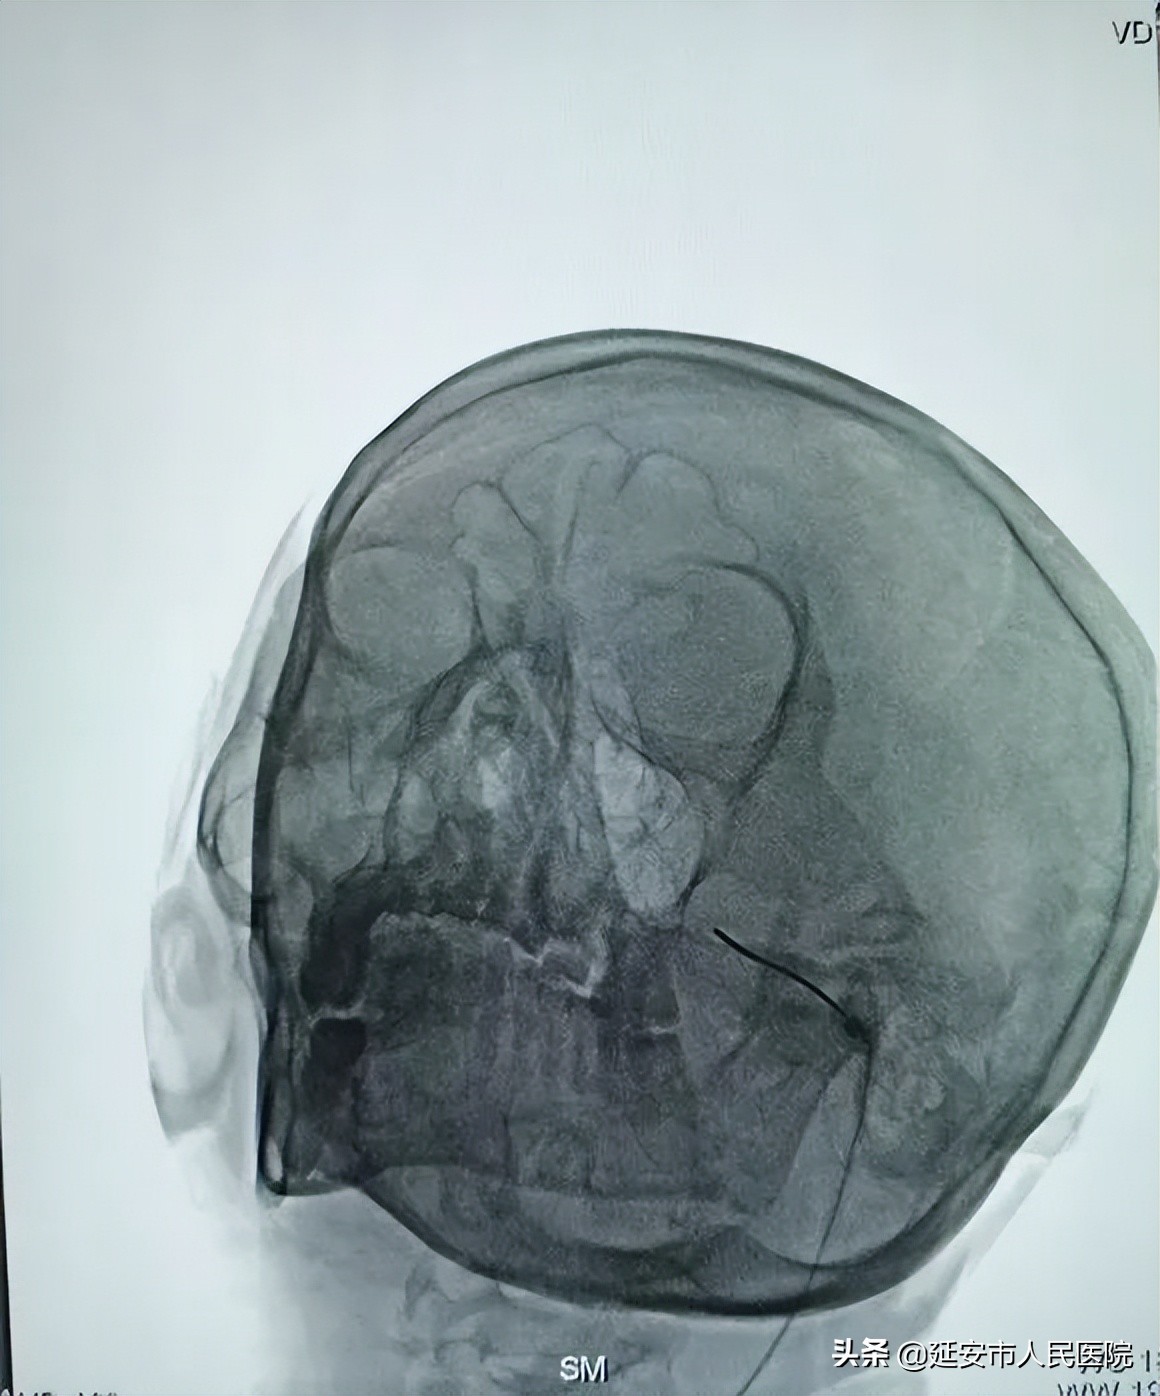

患者张大娘今年62岁,于8年前无明显诱因出现左侧颜面部疼痛,疼痛呈阵发性针刺样疼痛,并向上颌部放射。诊断:三叉神经痛,在多处诊治(针灸、理疗、药物)效果不佳,明显影响生活。经医生介绍来到我院就诊。李昔胜副主任医师经过详细查体,诊断为左侧原发性三叉神经痛(上颌支)。于7月7日由王忻主任医师主刀,在局麻下行左侧三叉神经(上颌支)射频热凝术。

目前,针对三叉神经痛的治疗方有保守治疗和手术治疗两种,传统的开颅手术,手术创伤大、风险高、费用高。射频热凝术又称“局麻下DSA引导下三叉神经射频热凝术”是目前治疗三叉神经痛最有效、最安全的微创手术。它通过射频针穿刺进入卵圆孔内的三叉神经节,射频针尖端产生热量,利用痛觉和触觉神经纤维对热度的耐受力不同,选择性阻断三叉神经纤维中传递痛觉的粗纤维,达到治疗疼痛又避免干扰面部正常感觉的目的。该技术在国内外已开展十多年,进行了大量的临床观察和研究,与其他治疗三叉神经的技术:如微血管减压、伽马刀等相比,具有疗效好、创伤小、花费低的优点。